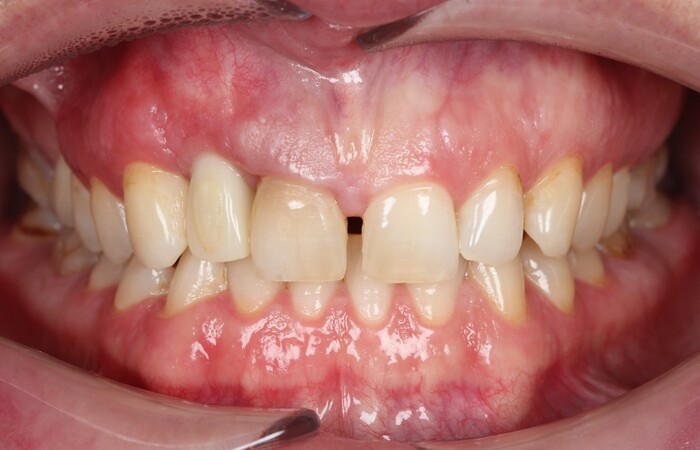

Далее проведена пластика десны, снова два месяца ожиданий и установка временной коронки:

Ну, такое, согласен, но это начало.

Еще через пару месяцев временную коронку сняли для изготовления новой:

И вот картинка спустя полгода «ношения» новой временной коронки: